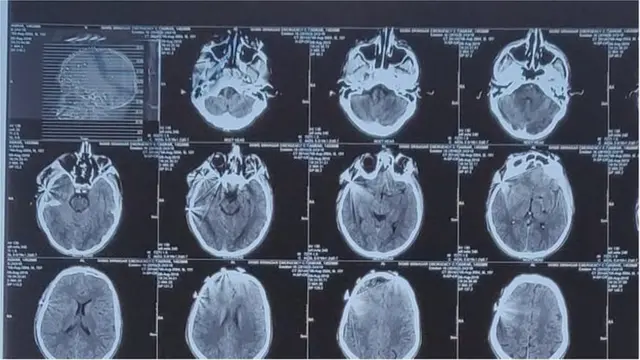

అస్రార్ మెడికల్ రిపోర్ట్

పెల్లెట్లు, టియర్ గ్యాస్ షెల్ పేలుడు వల్ల తగిలిన గాయాలతోనే అస్రార్ మృతి చెందాడని అతడి మెడికల్ రిపోర్టు చెబుతోంది.